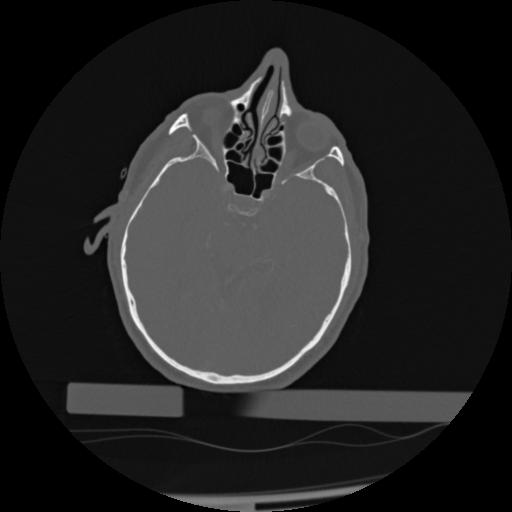

22 ANGIO,CE,Vol,0.5,ANGIO,,